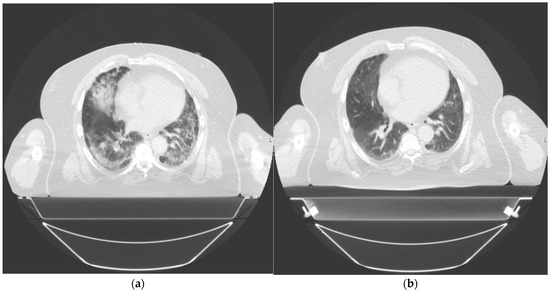

Figure 3. Thorax computed tomography (CT) taken of patient 2 at (a) day 1 prior to treatment and (b) day 42 post treatment.

After the single dose of LDRT, we observed clinical, biochemical, and radiological improvement. Prior to LDRT, the patient required 40% oxygen to maintain saturations of 96%. Forty-eight hours after LDRT, oxygen saturations were maintained at 92% on room air. His P/F ratio improved from 225 mmHg/F to 305 mmHg/F. Biochemically, his inflammatory markers improved with CRP dropping from 50.2 mg/dL at baseline to 3.9 mg/dL five days after LDRT. Serum BNP also reduced from 810 ng/L pre-radiotherapy to 439 ng/L five days post radiotherapy. Lymphocyte nadir was 0.81. A CT thorax scan performed at 42 days post radiotherapy no longer demonstrated bilateral pulmonary infiltrates although some patchy subpleural ground-glass changes persisted [Figure 3]. There was no fibrosis noted.